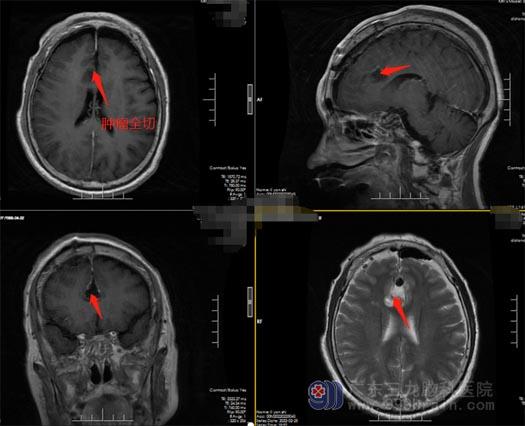

直到头痛症状加重,忍受不了的李阿姨把病情告诉了女儿,女儿连忙把她带到医院做检查,头颅MRI提示:前额部大脑镰旁异常信号,考虑肿瘤病变可能,脑膜瘤未排。“医生跟我们说妈妈脑袋里面长了肿瘤,还要做开颅手术,我们都很害怕,更加担心手术后恢复不好。”李阿姨的女儿说到。

经过全家人的多方打听,得知广东三九脑科医院神经外五科治疗团队是具有丰富治疗经验的脑科团队,女儿急忙带上李阿姨来到了广东三九脑科医院。头颅 MRI 显示额部跨大脑镰深部两侧占位性病变,考虑脑膜瘤可能性大;完善术前准备后,鲁明副院长、王国良主任带领神经外五科的医生团队在全麻下为李阿姨实施了“前额部大脑镰脑膜瘤切除术,术中肿瘤全部切除,手术顺利结束。

▲术前